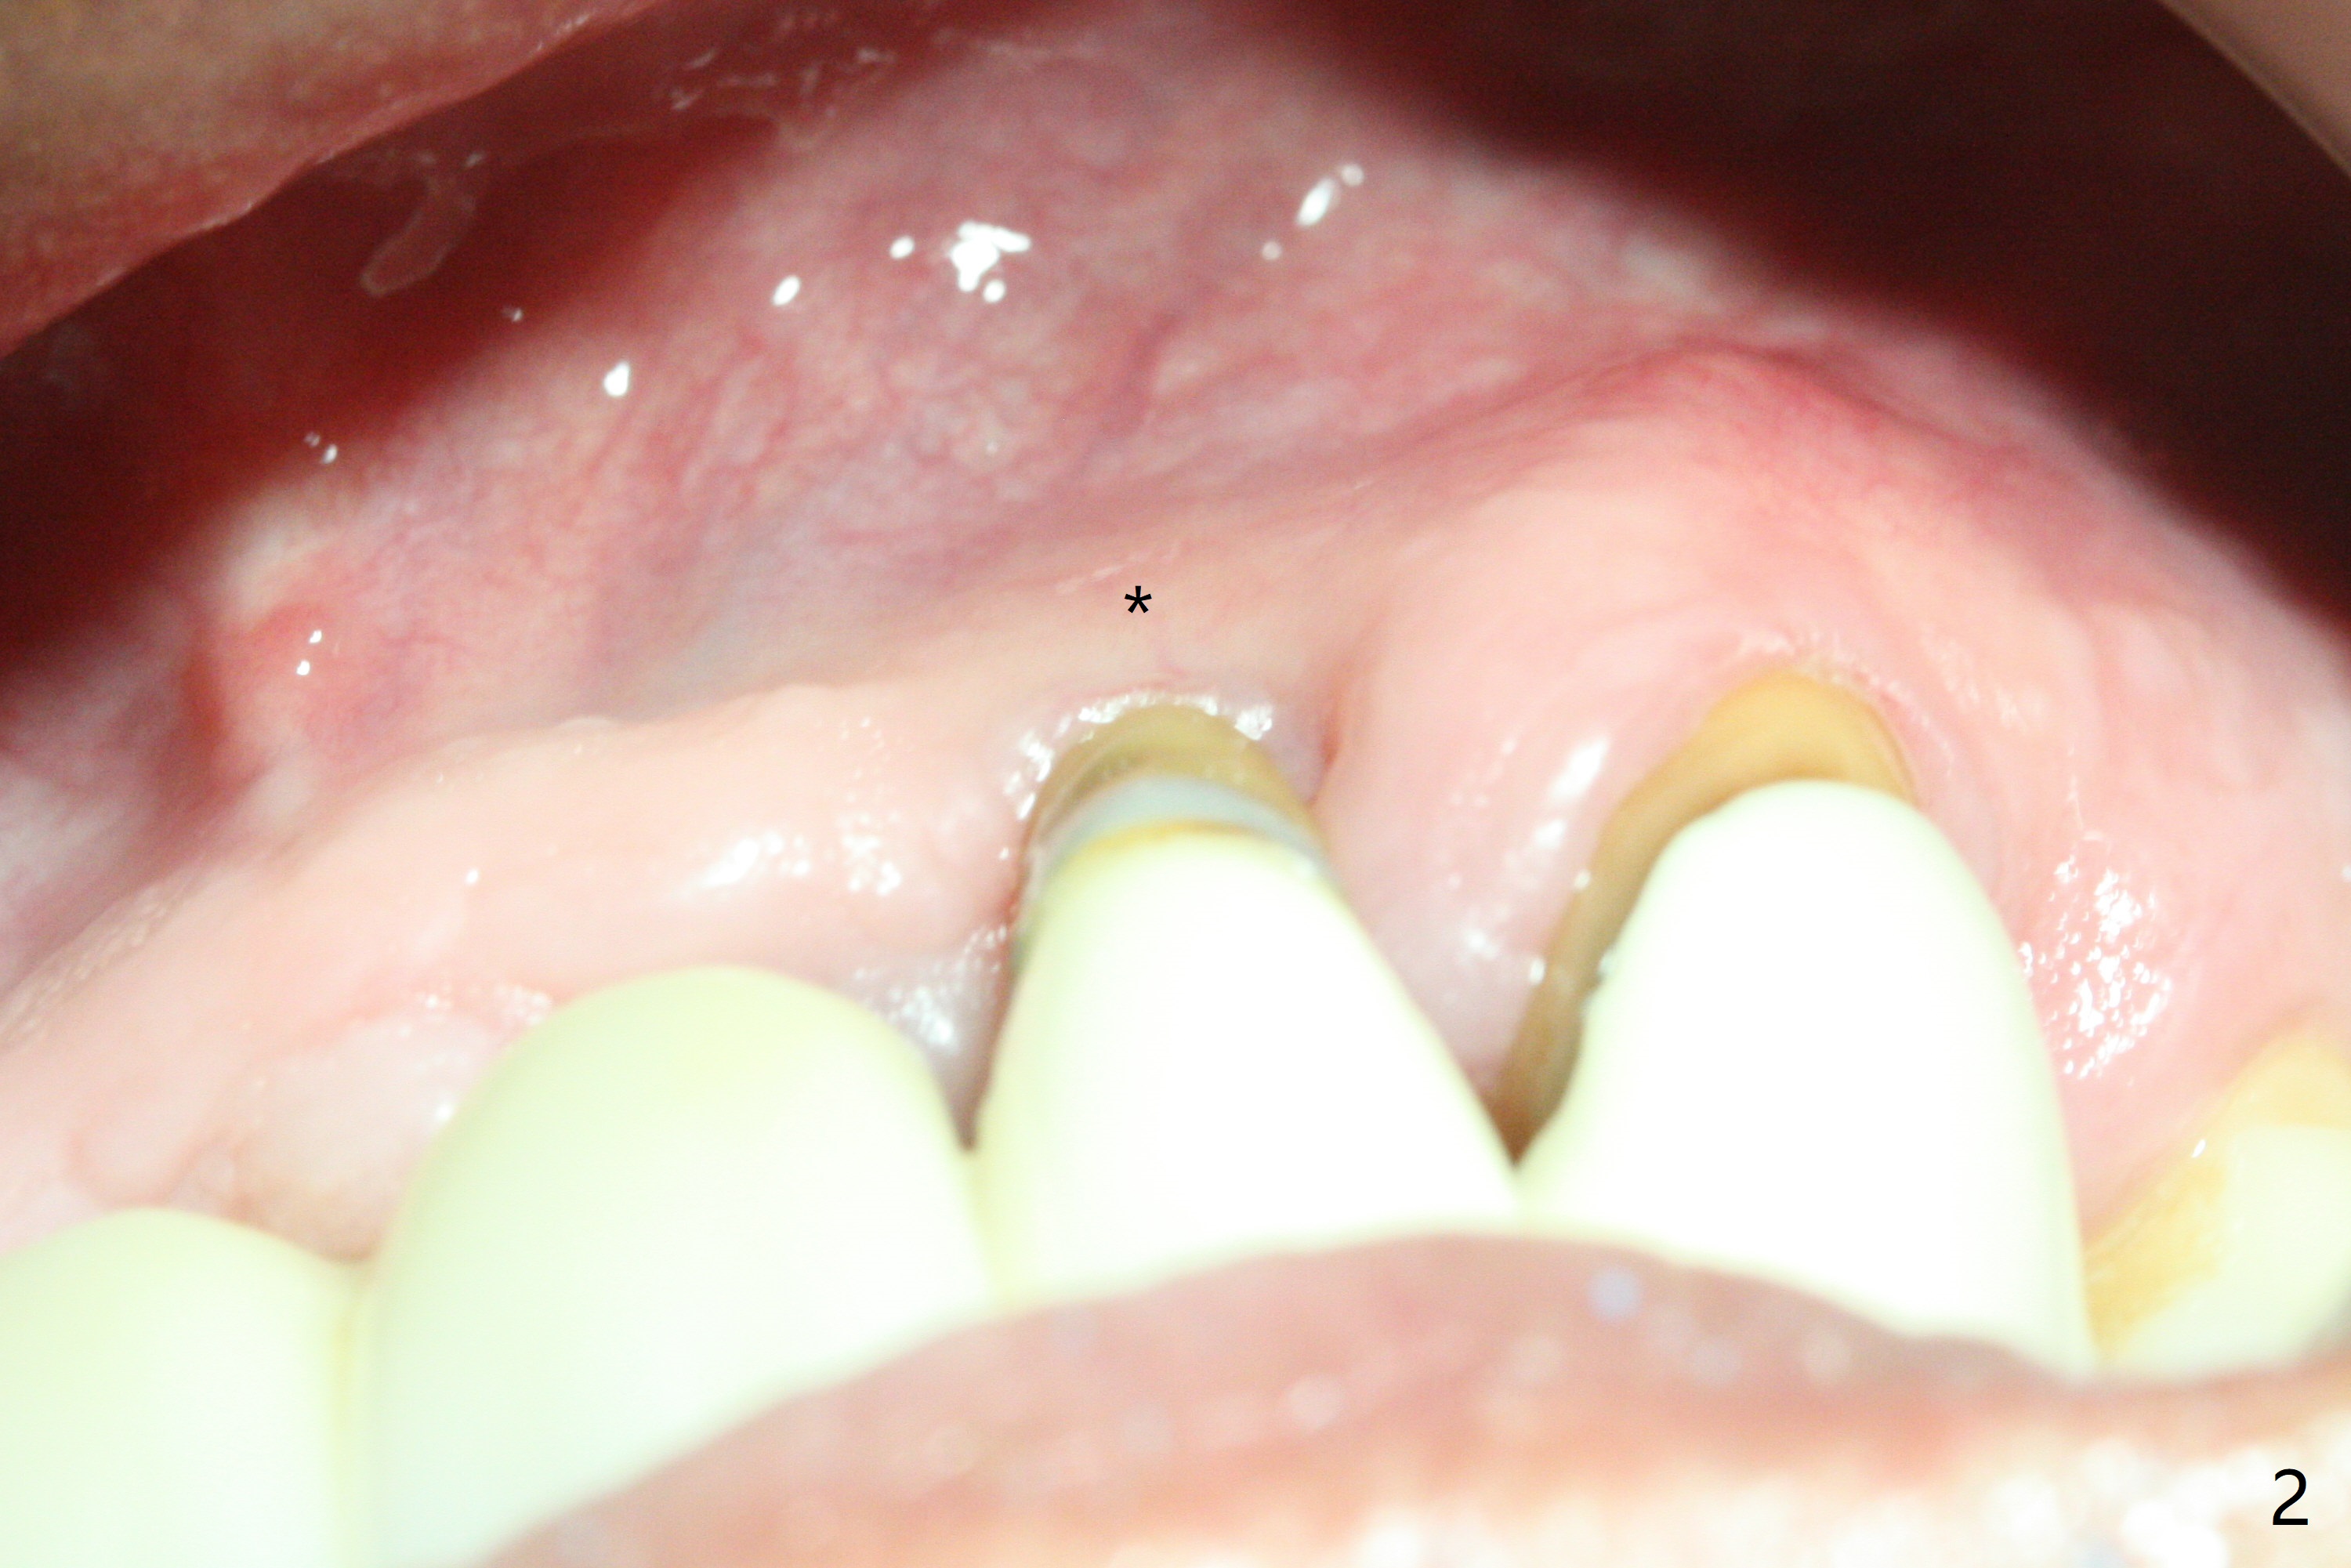

The tooth #10 has severe gingival recession (Fig.1) with loss of the buccal plate (Fig.2 *). After the initial osteotomy depth (Fig.3) increases by 2 mm, a 2.5x14(2) mm 1-piece implant is placed with insertion torque >60 Ncm (Fig.4). Palpation indicates the native bone apparently wider than CT shows. There is no sign of buccal or palatal plate perforation by palpation during osteotomy or implant placement. Vera Graft is placed repeatedly around the coronal threads (Fig.5-7 *). An immediate provisional is fabricated to close the socket (Fig.8). The buccal plate appears to collapse 1 month postop (cortical plate graft apparently more appropriate in this case); the margin of the provisional is trimmed so that the gingiva may grow incisally (Fig.9). The provisional dislodges several times postop due to short abutment. By nearly 4 months postop, the coronal bony defect seems to have been repaired (Fig.10 *). The tooth #11 has tenderness with bone loss (Fig.10 ^), corroborated by CT (distal bone loss, Fig.11 *). Since the apical bone is narrow (Fig.12), a narrow long implant is expected (Fig.13). Use an implant (3.5x13 mm) consistent with those at #14 and 15.